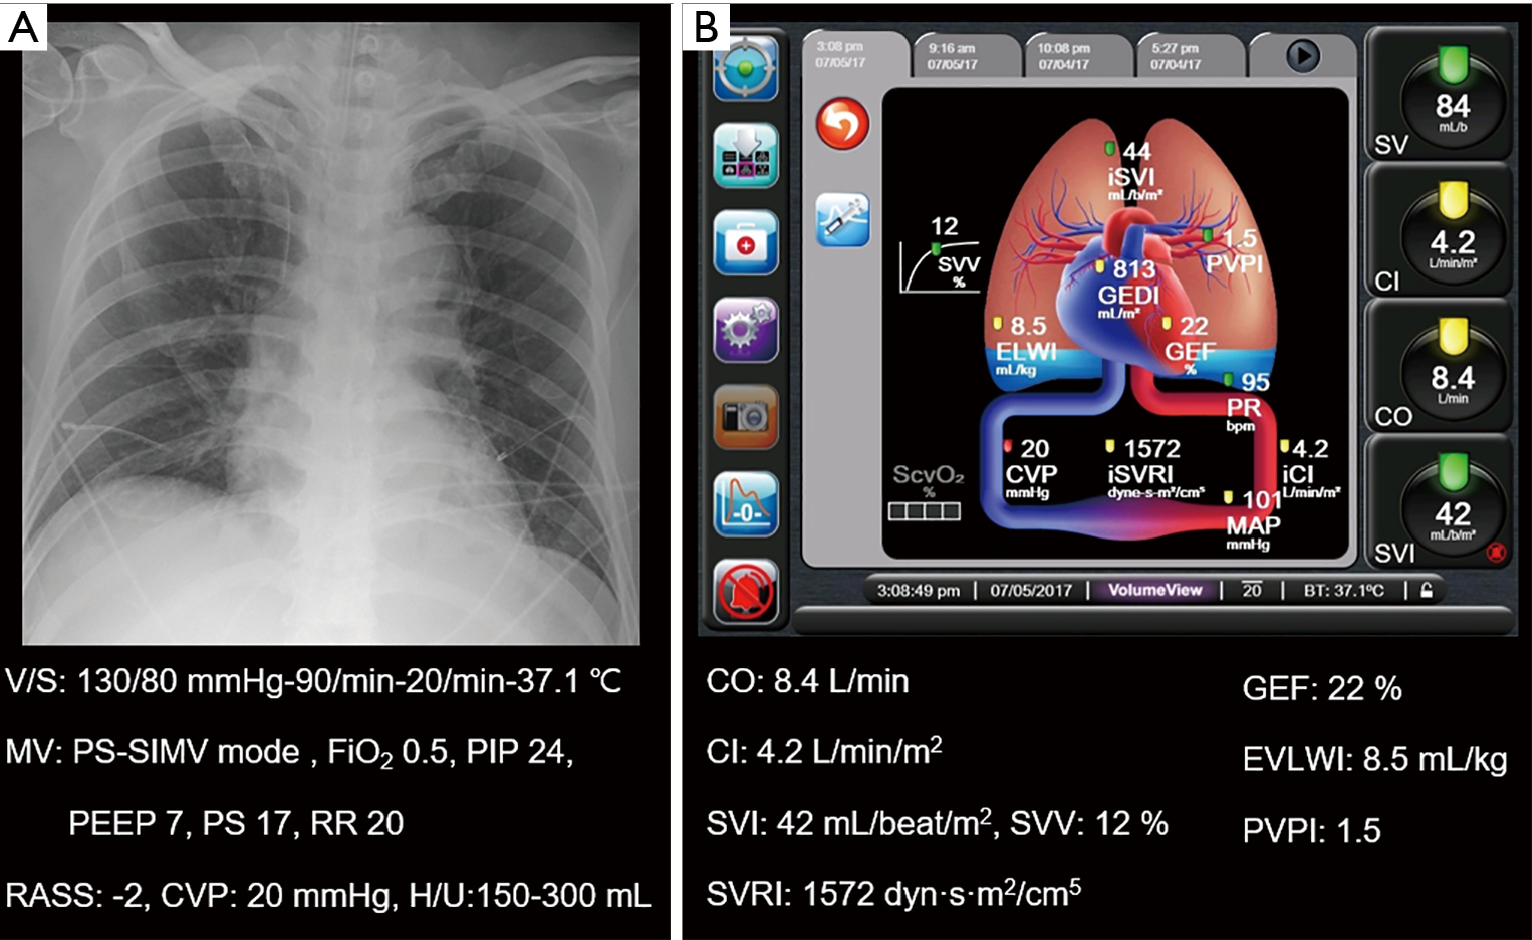

Are management decisions in critical patients changed with use of What Is Transpulmonary Thermodilution Transpulmonary thermodilution is an invasive technique of bedside volumetric hemodynamic monitoring providing valuable. In this review, transpulmonary thermodilution (tptd) as a bedside tool to quantitatively monitor lung water accumulation. Transpulmonary thermodilution is a technique that provides a full haemodynamic assessment through cardiac output and other indices. The emerging role of transpulmonary thermodilution (tptd) quantitative evlw measurements in the perioperative period. What Is Transpulmonary Thermodilution.

Transpulmonary thermodilution and pulse pressure variations in a septic What Is Transpulmonary Thermodilution Transpulmonary thermodilution is a technique that provides a full haemodynamic assessment through cardiac output and other indices. In this review, transpulmonary thermodilution (tptd) as a bedside tool to quantitatively monitor lung water accumulation. The emerging role of transpulmonary thermodilution (tptd) quantitative evlw measurements in the perioperative period as a new tool to guide fluid therapy and. Transpulmonary thermodilution is an. What Is Transpulmonary Thermodilution.